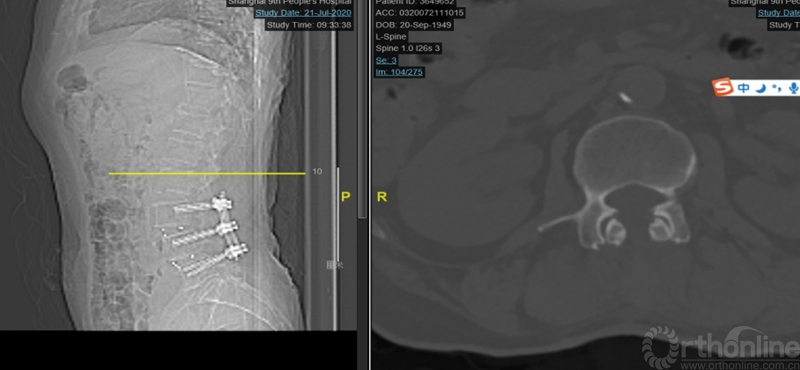

术中工作通道建立在右侧症状侧,在显微镜下以右侧单侧症状侧椎管减压为主;工作通道头倾21度,平行椎间隙方向安置(腰3-4椎间隙与水平成角21度,图2),术中矢状面近端减压时,尽量向头端摆动和扩张工作通道,矢状面近端减压范围停止于腰椎矢状面前凸的顶椎远端(图5)。

图4:第一次术后X ray

图5:第一次手术近段减压交界区腰3下椎板

本病例显示:因MIS-TLIF工作通道的远近端摆动角度的范围决定了矢状面头尾端的减压范围,若面对高PI显著腰椎前凸的多节段腰椎管狭窄的病例,近端扩大减压会受到一定限制。